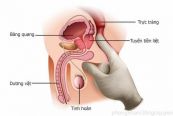

Nội soi bàng quang được thực hiện bởi bác sĩ tiết niệu, với một hoặc nhiều trợ lý, thủ thuật được thực hiện trong bệnh viện hoặc phòng của bác sĩ. Để hiểu rõ hơn về thủ thuật này, mời các bạn tham khảo bài viết dưới đây!

Kiểm tra trực tràng kỹ thuật số có thể được thực hiện để kiểm tra các vấn đề với các cơ quan hoặc các cấu trúc khác trong khung chậu và bụng dưới. Dưới đây là thông tin chi tiết về phương pháp này, mời các bạn tham khảo!